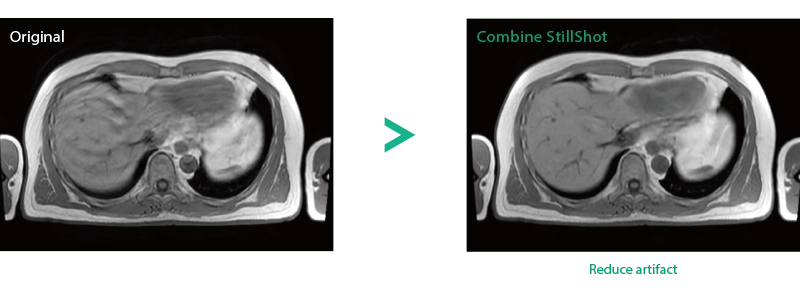

Reduce artifacts caused by patient movement, such as coughing or sneezing, by post reconstruction.

When motion artifacts occurs in the image due to coughing, sneezing, or involuntary movements, either or both the visual information acquired by monitoring cameras, Synergy Vision, and the intrabody information acquired by the navigator pulse can be used to provide an image with reduced artifacts. This reduces the re-imaging rate.

Body movements that affect image quality are detected from monitoring cameras based on thresholds derived for each body part.

Movements within the body are detected by navigator pulses. Body movements that significantly affect image quality are detected based on the error between pulses.